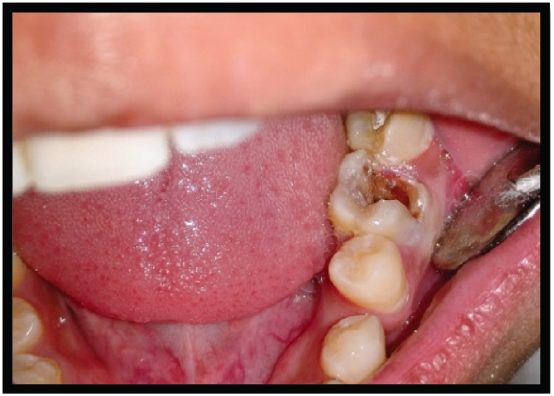

Figure 1. Grossly carious tooth

thumb